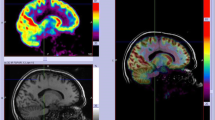

A successful illustrative case of full correlation of PET, SPECT, and ESI is shown in Figs. 2 and 4. A more complicated case is shown in Fig. 3.

Female patient, 40 years with epilepsy since age of 14 y. All three imaging modalities (PET + SISCOM + ESI) were concordant for the left temporal pole, confirmed by phase II with depth electrodes. Morphometry was not carried out in this patient, due to lack of access at that time. Left temporal polectomy with amygdalo-hippocampectomy was carried out and she was seizure-free (follow-up 5 years)

This 19 years old female ETLE patient was known for seizures since the age of 4. All three imaging modalities (PET, SPECT, ESI) were concordant for the insular region and the frontal and temporal opercular region. She was operated at the age of 7 years and resection resulted in an excellent outcome (ILAE I) after 12 years of follow-up. No phase II was carried out prior to surgery, due to complete concordance of the results. Blue: maximum perfusion of ictal SPECT, green: ESI, red: PET metabolism is found in red with an area of absent concordant with ESI and ictal SPECT. Left is left in this and all figures